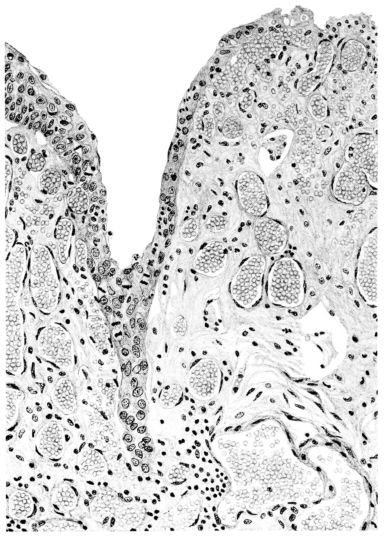

FIG. III. AUTOPSY NO. 90. DRAWING FROM A LESION OF THE TRACHEA (SOMEWHAT OLDER THAN THAT ILLUSTRATED IN FIGURE II). THE MUCOSA IS ENTIRELY LACKING. CONGESTION AND EDEMA ARE THE STRIKING FEATURES IN THE SUBMUCOSA. THE NECROTIZING PROCESS HAS EXTENDED INTO THE MUCUS GLANDS. THIS IS SHOWN IN THE LOWER PICTURE.

The changes are less marked, perhaps, in the trachea than in its finer ramifications. The mucosa is constantly more or less destroyed and large areas, usually focal, are entirely devoid of their epithelial covering. This is replaced by a sparse exudate, composed largely of red blood cells, mucus, a small amount of fibrin, and nuclear fragments (Fig. II). It may dip into the submucosa for a short distance, but usually these indentures are associated with the ducts of the mucous glands into which the inflammatory reaction extends. A more striking feature than the exudate, however, is the edema and the congestion of the submucosa. The loose areolar tissue of the submucosa is spread widely apart, and throughout it distended blood vessels are very conspicuous. Occasionally such a vessel is broken and actual hemorrhage appears in the submucosa. Occasionally, too, the inflammation extends down the duct to the mucous gland itself, and here, also, aplastic inflammatory reaction is evident, inasmuch as the acini now stain intensely red with the cells undifferentiated from each other and specked here and there by broken remains of the dead nuclei (Fig. III). After the disease has continued for a short period, even at the end of five or six days, some regeneration of the epithelial lining may be seen (3) (Fig. IV). But despite this, the acute picture persists, and there goes on, side by side, an attempted repair characterized by epithelial regeneration and the same evidence of acute change. Since the lesion is essentially a superficial one, scars or contractures of any extent are not encountered in the trachea, even in examples of the disease that have ended fatally only after many weeks.[4]